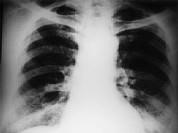

问题 女,34岁,新月体肾炎患者,最近咳嗽咯血,第一次行胸片检查考虑为双下肺感染,抗感染治疗后无明显好转,症状加重,4天后复查并行CT检查如图,应考虑为 ( )

选项 A.肺泡蛋白沉着症 B.肺含铁血黄素沉着症 C.双下肺肺炎 D.肺出血肾炎综合征 E.韦格肉芽肿

答案 D